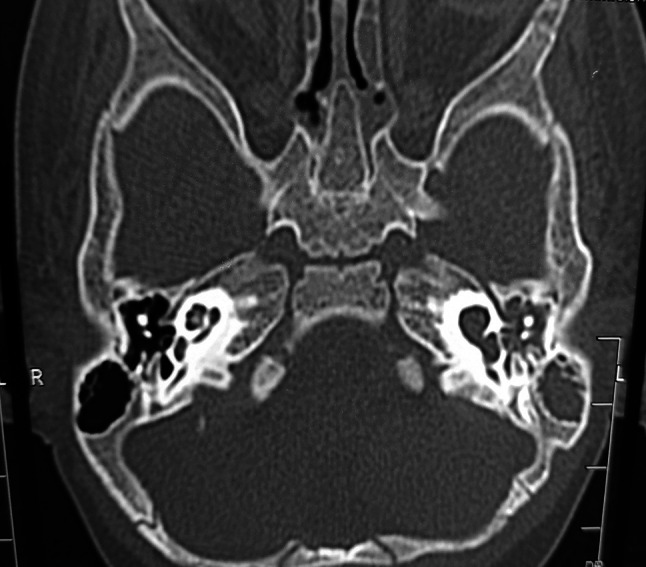

Left inner ear Sennaroglu IP-1 defect/SMS typeIIIb cochleovestibular malformation soft tissue density in left middle ear

High-resolution temporal bone CT scan was done which confirmed the inner ear findings of MRI. Considering the examination and radiology we assumed that a previous episode of meningitis was due to the left ear congenital malformation that led to CSF leak.